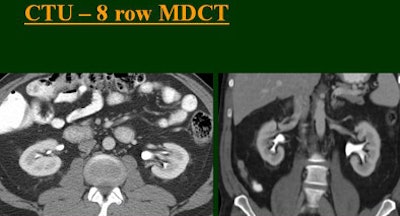

At the 2004 RSNA meeting in Chicago, Dr. Vassilios Raptopoulos from Massachusetts General Hospital and Harvard Medical School in Boston evaluated single-, four-, eight-, and 16-row detector scanners in 200 patients using a single-acquisition biphasic CT urography (CTU) protocol. As the number of detector rows increased, visualization -- especially of the calyces -- improved significantly.

"As we've been scanning through the kidneys, we've been noticing that there has been an increase in the quality images as we go from (single-) to four-, eight-, and 16-row detector scans," Raptopoulos said. "Our purpose, then, was to assess the quality of CTU with progressively improving CT technology from (single-) to 4-, 8-, and 16-row scanners, using a split-injection single scanning technique."

| Top to bottom: Split-bolus CTU improves significantly using a nearly identical protocol but with the addition of more detector rows, from single- (spiral), four-, eight-, and 16-row scanners. All images courtesy of Dr. Vassilios Raptopoulos. |

The single-row scanner required two breath-holds; the other scanners reduced scan time from about 20 seconds (four-slice) down to seven seconds (16-slice). Collimation for the single-row scanner was 5 mm, with 3-mm overlapping reconstructions. Collimation for the four-, eight-, and 16-row scanners was 2.5 mm, 1.5 mm, and 0.5 mm, respectively, with the patients scanned in a prone position.

Based on multiplanar reformatted (MPR) images, there was significant upscale improvement in calyceal detail from the isotropic images provided by single-detector scanning (median score 2) to four- (median score 3), eight- (median score 4), and 16-detector scanning, Raptopoulos said. On MPR images the calyceal were 1, 2, 3, and 5, respectively. The median ureteral filling was 4 for the upper and left-lower ureters, and 3 for the right-lower ureters.

"We're using this technique of biphasic injections not only in CTU, but in general abdominal scanning in trauma, in renal CT, and we can see the renal vessels quite well in relation to the collecting systems," Raptopoulos said. "Combined excretory- and parenchymal-phase CTU is a practical technique, allowing a decrease in patient scanning," he said. "Sixteen-row CTU with the patient in a prone position significantly improves the quality of the exam."